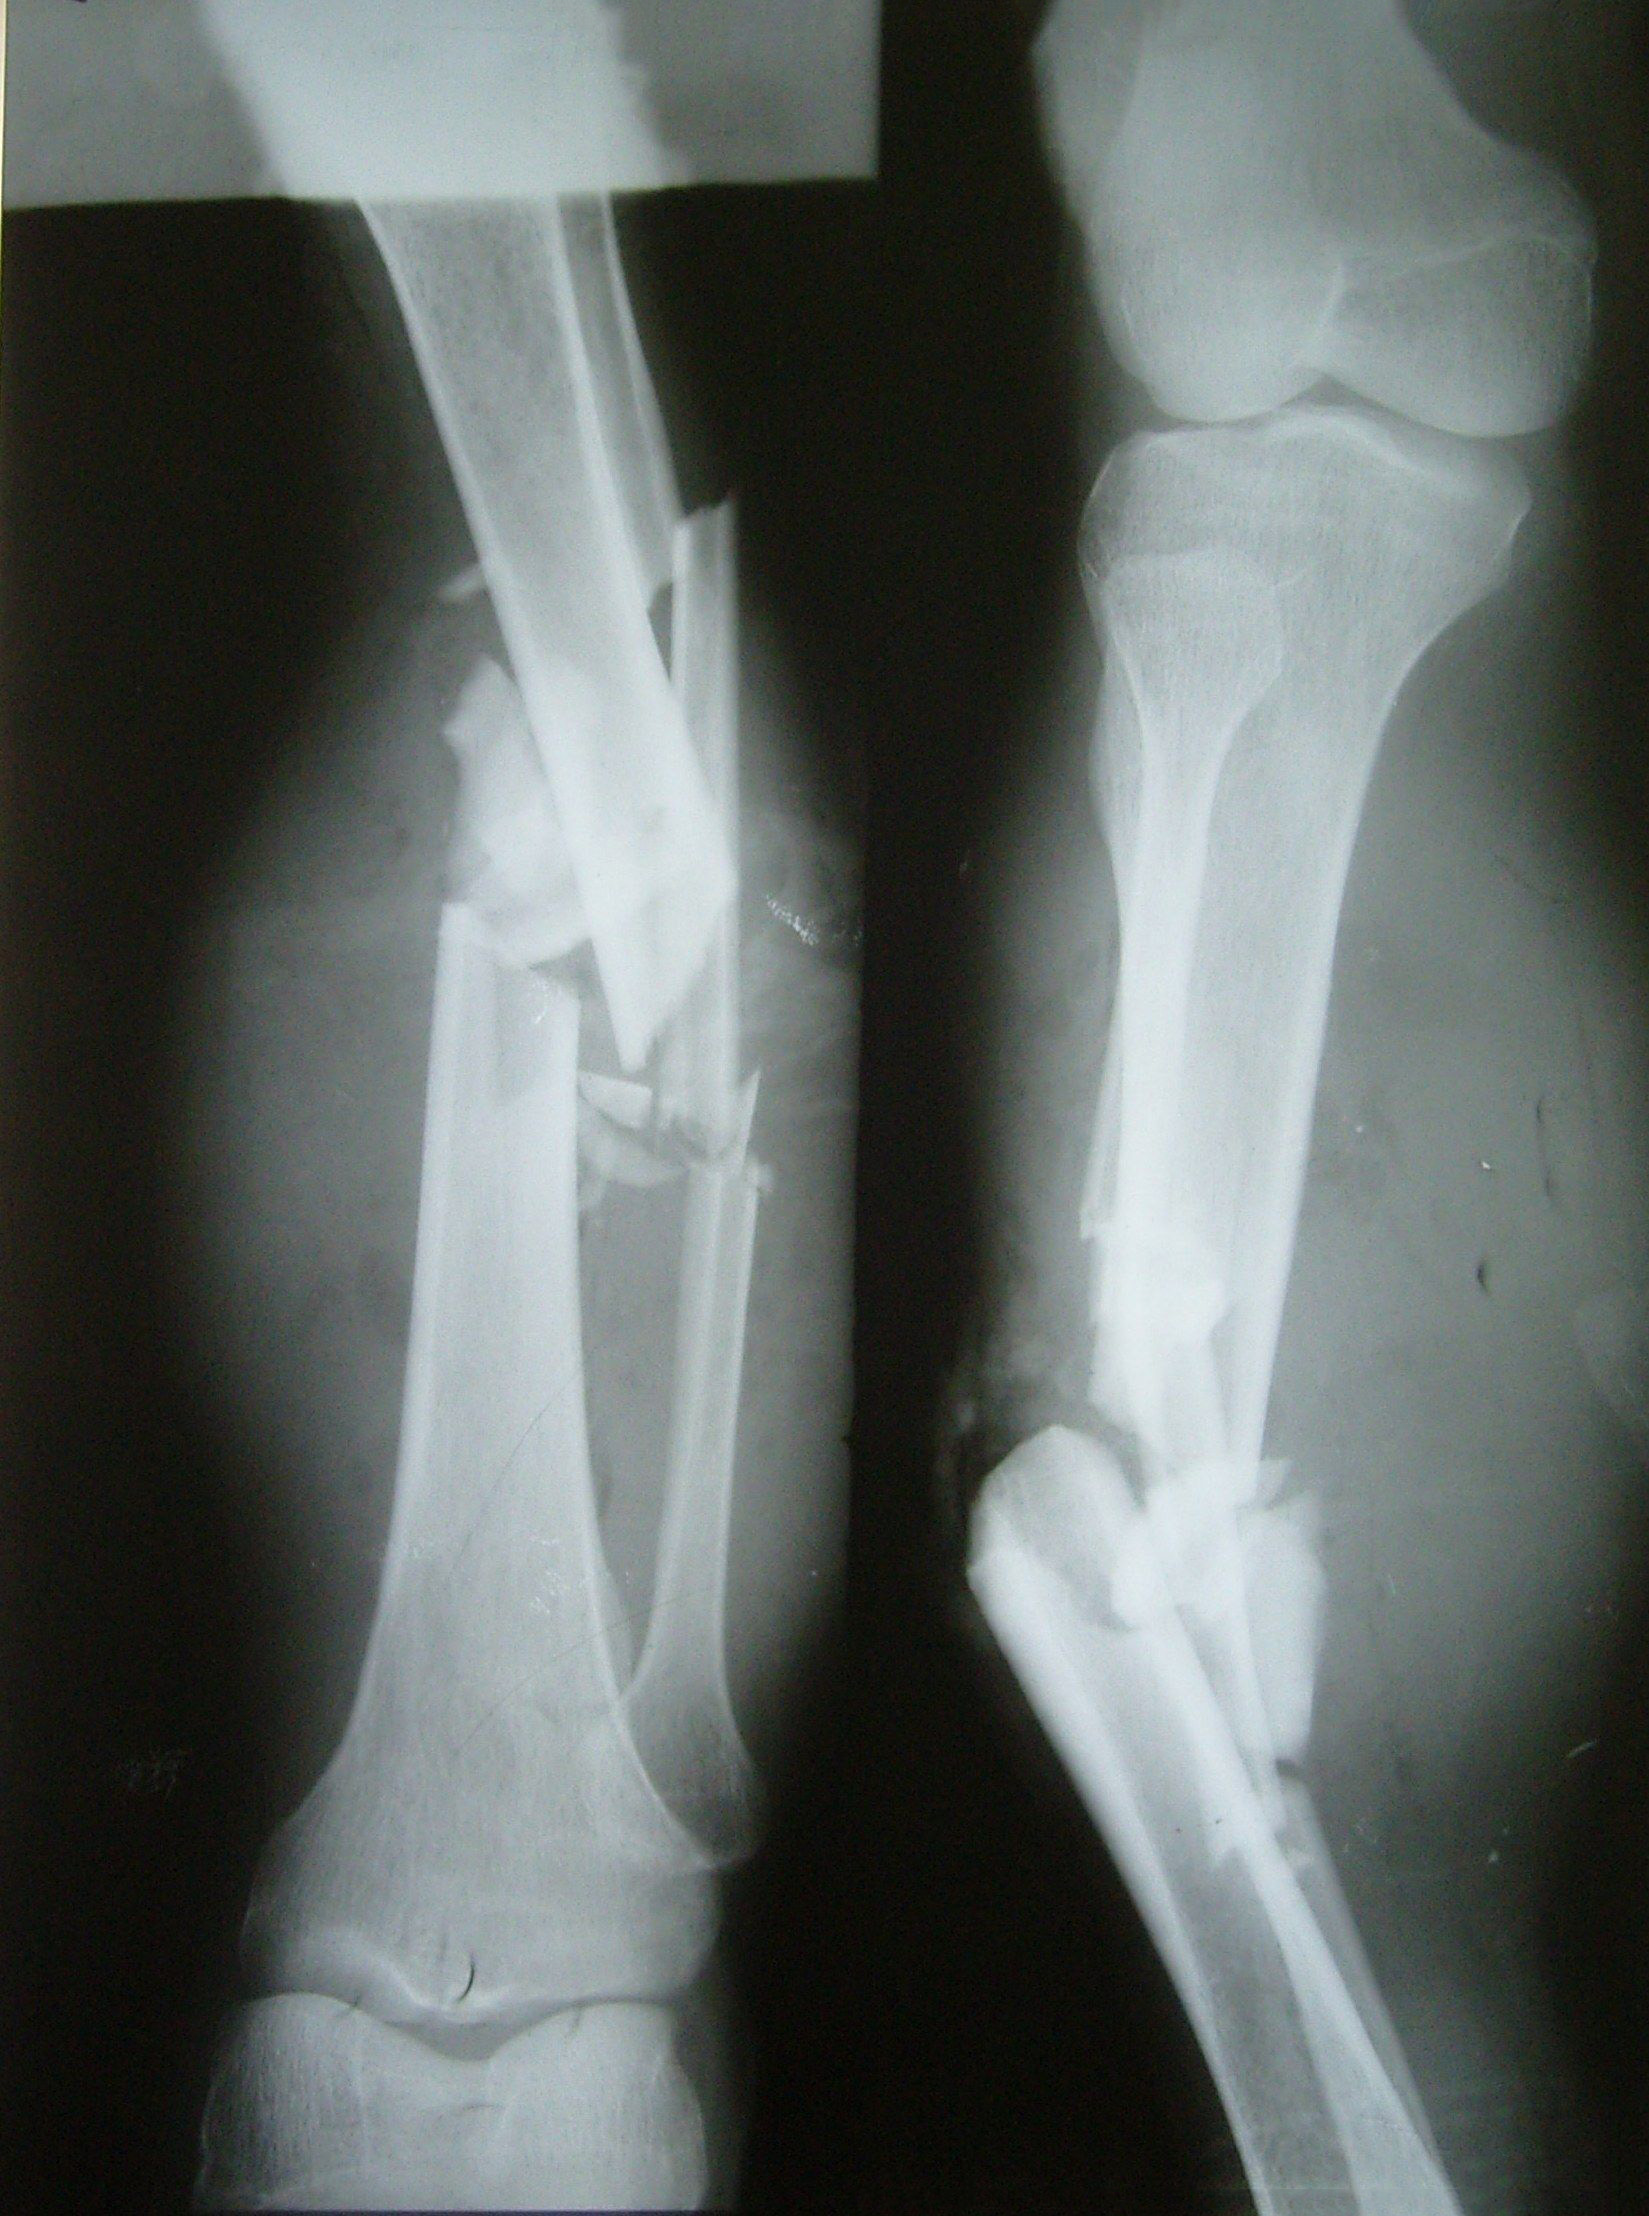

開(kāi)放性骨折的定義及應(yīng)急處理

凡骨折時(shí),合并有覆蓋骨折部位的皮膚及皮下軟組織損傷破裂,使骨折斷端和外界相通者,稱(chēng)為開(kāi)放性骨折。開(kāi)放性骨折是創(chuàng)傷骨科的常見(jiàn)病、多發(fā)病,隨著社會(huì)的發(fā)展,現(xiàn)代化高速工具的使用,所造成的開(kāi)放性骨折日趨嚴(yán)重,病情越發(fā)復(fù)雜、治療更加困難。

開(kāi)放性骨折癥狀

局部表現(xiàn)

肱骨髁上骨折

2、骨折的特有體征

(1)畸形:骨折段移位可使患肢外形發(fā)生改變,主要表現(xiàn)為短縮、成角或旋轉(zhuǎn)?!?br />   (2)異常活動(dòng):正常情況下肢體不能活動(dòng)的部位,骨折后出現(xiàn)不正常的活動(dòng)。

(3)骨擦音或骨擦感:骨折后,兩骨折端相互摩擦?xí)r,可產(chǎn)生骨擯音或骨擦感。